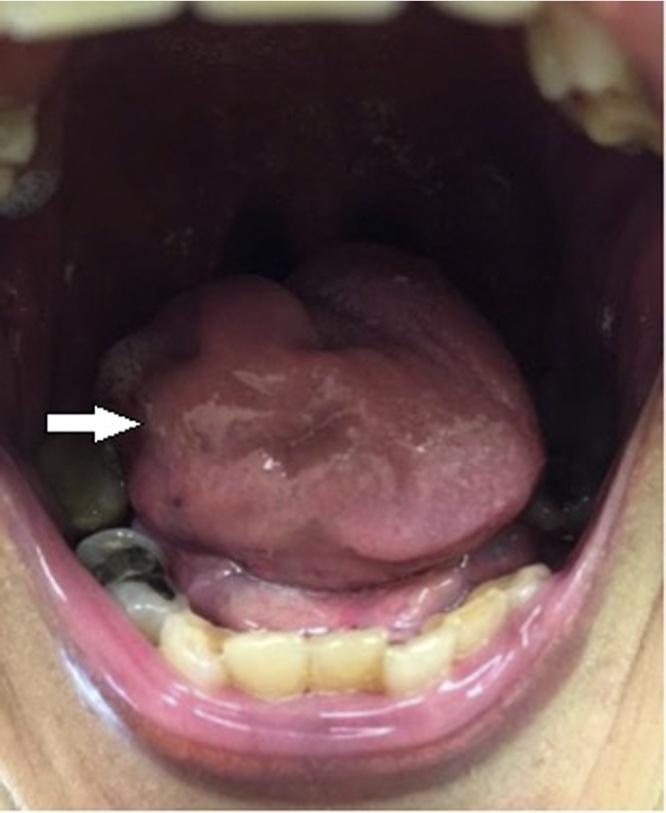

A 63year old Malay female presented with progressive dysphagia and slurred speech for one year. Physical examination showed unilateral right tongue wasting, fasciculation and deviation to the right. An MRI showed atrophy of the tongue due to denervation and subsequently she was treated in a neurology clinic for 8 months. Due to lack of improvement, she was referred to our surgical unit and underwent examination under anaesthesia (EUA) and biopsy. Histology showed adenoid cystic carcinoma with perineural involvement, resulting in lower motor neuron signs. She underwent radiotherapy to the base of her tongue (70Gy/35#). A PET-CT one month post treatment showed complete response.

一名63岁的马来女性,出现进行性吞咽困难和言语不清一年。体格检查显示右侧舌肌单侧萎缩、肌束震颤并偏向右侧。磁共振成像(MRI)显示由于去神经支配导致舌肌萎缩,随后她在神经科诊所接受了8个月的治疗。由于病情没有改善,她被转诊至我们的外科病房,接受了麻醉下检查(EUA)和活检。组织学检查显示为腺样囊性癌伴神经周围受累,导致下运动神经元体征。她接受了舌根部放疗(70Gy/35次)。治疗后一个月的正电子发射断层扫描(PET-CT)显示完全缓解。